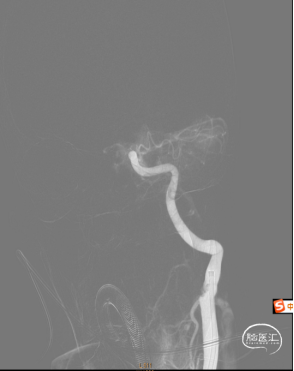

造影可见左侧颈总动脉闭塞、左侧大脑中动脉通过前交通向左侧大脑供血。

通过6F抽吸导管应用50ml注射器负压抽吸出大量暗红色血栓后,造影可见左侧颈内动脉后交通段显影。

再次应用6F抽吸导管抽吸,仍有少量暗红色血栓抽出,造影可见左侧大脑前动脉及左侧大脑中动脉。大脑动脉M1远段未见显影(血栓逃逸)。